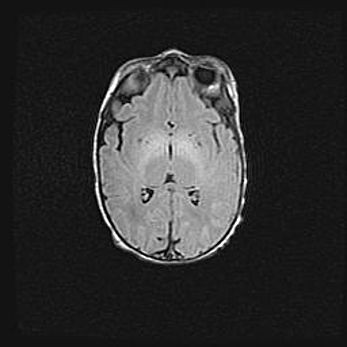

Множественные кисты обоих полушарий головного мозга, наибольшая из них в правой затылочной области. Ассиметричная атрофическая гидроцефалия.

Возраст: 7 месяцев

Вес: 5660 г

Пол: мужской

Окружность головы: 41,5 см

Срок гестации: 28-29 недель

Кисты головного мозга развиваются в результате многоочаговых некрозов вещества мозга и возникают вследствие перенесенной перинатальной инфекции, менингитов, энцефалитов, асфиксии, родовой травмы, расстройств мозгового кровообращения различного генеза. Образованию кист в веществе головного мозга плодов и новорожденных способствуют такие факторы, как высокое содержание в нем воды, недостаточная (или отсутствие) миелинизация и слабая астроглиальная реакция на повреждение.

Кисты могут сочетаться с гидроцефалией и другими поражениями головного мозга.